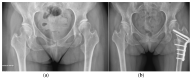

Osteoarthritis is a degenerative condition affecting the whole joint with the underlying bone, representing a major source of pain, disability, and socioeconomic cost worldwide. Age is considered the strongest risk factor, albeit abnormal biomechanics, morphology, congenital abnormality, deformity, malalignment, limb-length discrepancy, lifestyle, and injury may further increase the risk of the development and progression of osteoarthritis as well. Pain and loss of function are the main clinical features that lead to treatment. Although early manifestations of osteoarthritis are amenable to lifestyle modification, adequate pain management, and physical therapy, disease advancement frequently requires surgical treatment. The symptomatic progression of osteoarthritis with radiographical confirmation can be addressed either with arthroscopic interventions, (joint) preservation techniques, or bone fusion procedures, whereas (joint) replacement is preferentially reserved for severe and end-stage disease. The surgical treatment aims at alleviating pain and disability while restoring native biomechanics. Miscellaneous surgical techniques for addressing osteoarthritis exist. Advanced computer-integrated surgical concepts allow for patient personalization and optimization of surgical treatment. The scope of this article is to present an overview of the fundamentals of conventional surgical treatment options for osteoarthritis of the human skeleton, with emphasis on arthroscopy, preservation, arthrodesis, and replacement. Contemporary computer-assisted orthopaedic surgery concepts are further elucidated.